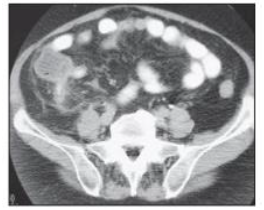

Paciente masculino de 45 anos dá entrada ao PA com dor em FID há 7 horas, inapetência e febre. Ao exame clínico, há dor à descompressão brusca da FID. A imagem tomográfica a seguir confirma o diagnóstico de